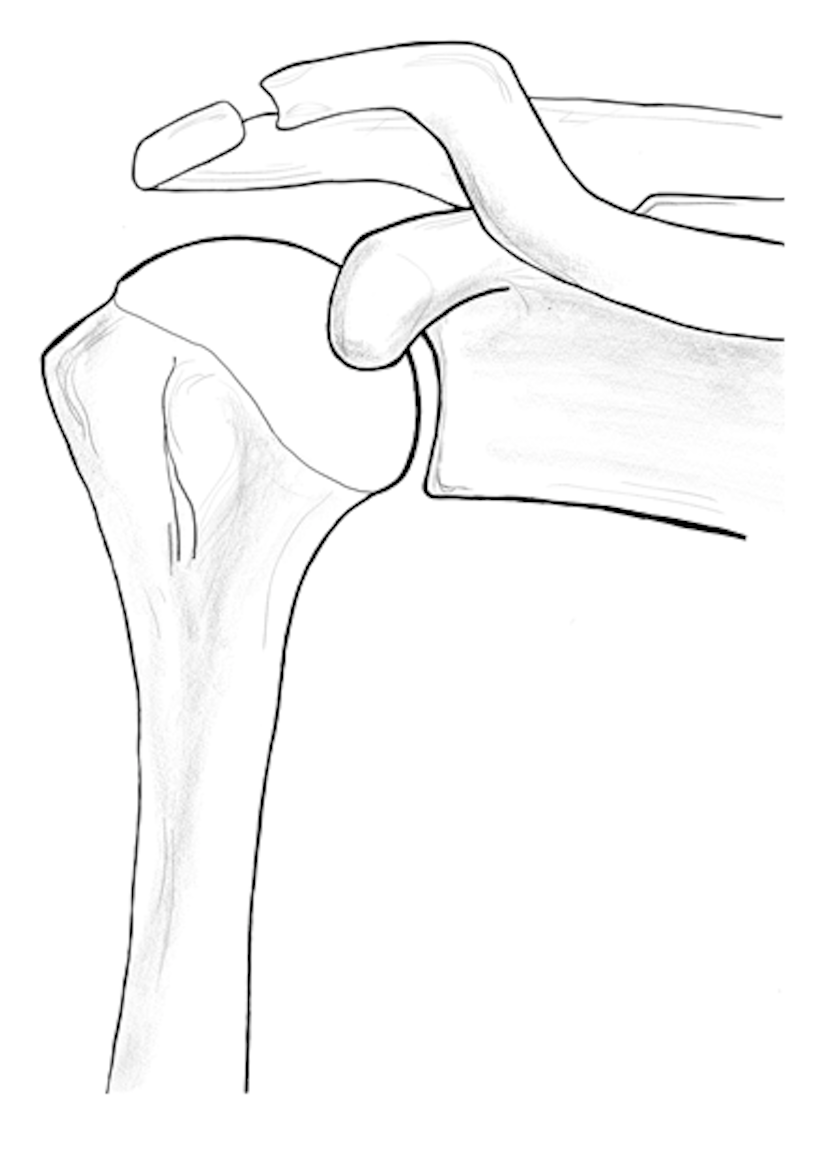

Shoulder Arthritis